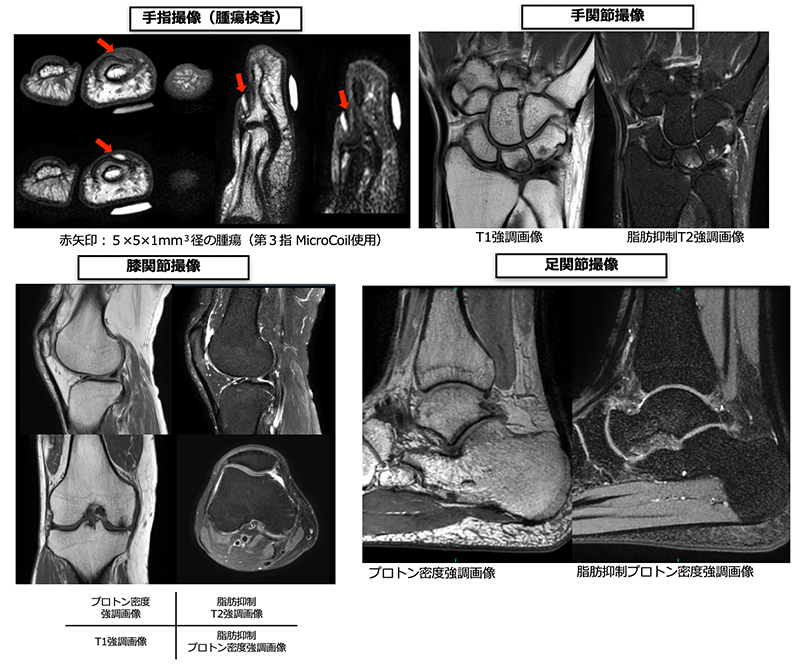

四肢領域では主に関節部が多く、手関節・肘関節・肩関節・股関節・膝関節・足関節など目的に合わせて検査を行っています。X線検査やCT検査では評価の難しい軟骨、筋肉、腱、靭帯などの軟部組織も明瞭に描出が可能なため、関節痛や靭帯損傷、骨折などの診断に有用です。